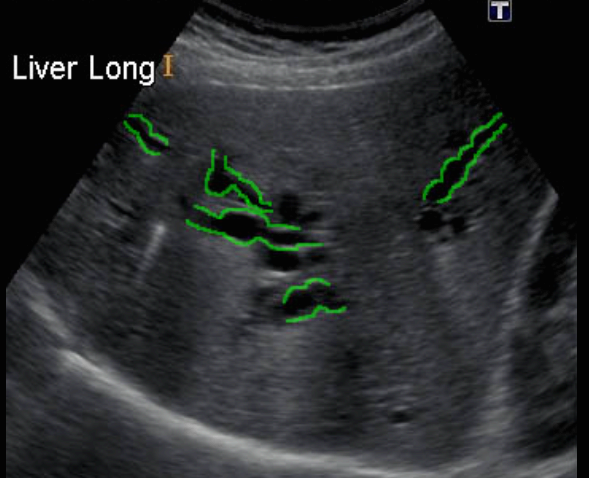

Choledocholithiasis US finding

- 총담관 내에 후방음향음영을 동반한 강한 에코가 관찰된다.

- 총담관의 확장 소견이 보인다. ( 7mm 이상)

- 담석이 관찰되지 않고 간외, 간내담관의 확장소견을 시사하는 엽총징후(shotgun sign)이나 평행관 징후(parallel channel sign)가 관찰되기도 한다.

- 엽총징후(shotgun sign): 간외 담관이 확장되어 간외 담관과 문맥이 이웃해 관찰된다.

- 평행관 징후(parallel channel sign): 간내 담관이 확장되어 인접하고 있는 문맥과 나란히 2개의 관상구조로 나타난다.